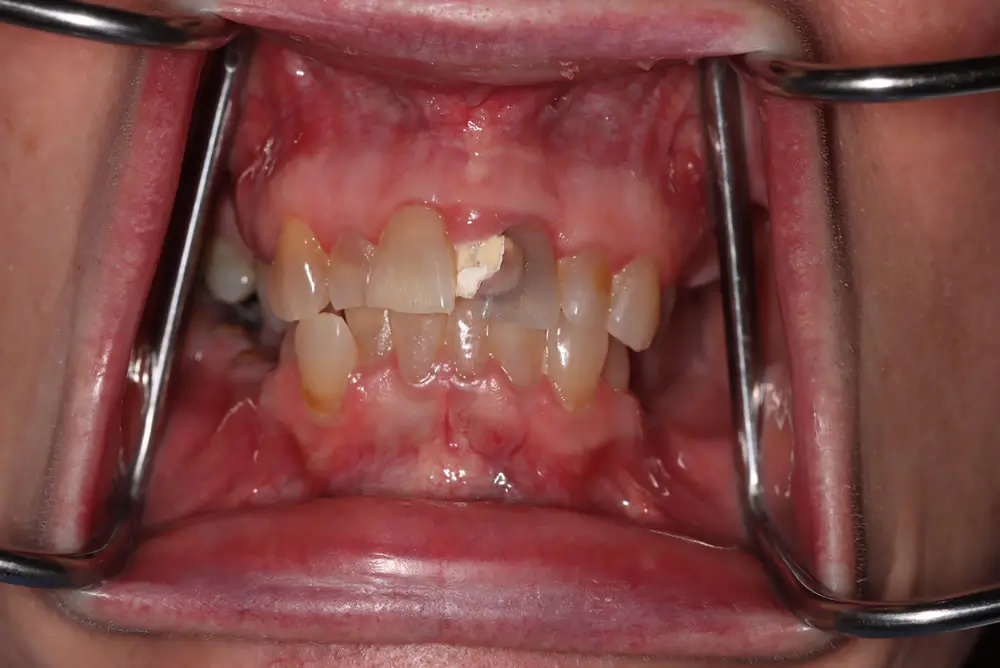

• Close-up of a mouth with dental retractors showing upper and lower teeth. The front upper teeth are discolored and misaligned, with visible gaps and signs of decay. Close-up of a person smiling, showing their teeth.